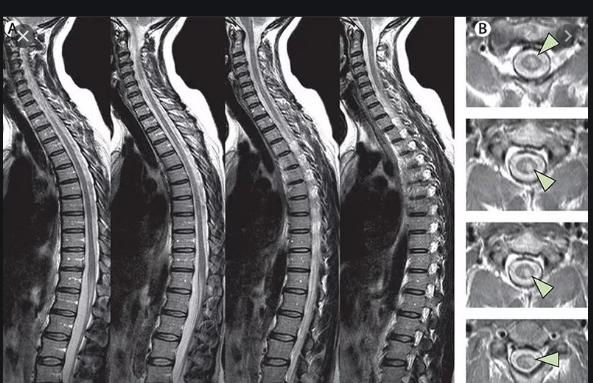

Як результат забою при нейровізуалізації спостерігаються крововиливи (гематомієлія), вогнища розтрощення, набряк, частковий або повний розрив спинного мозку.

КТ та МРТ – це золотий стандарт діагностики при спінальній травмі.

Золотим стандартом в діагностиці струсу спинного мозку є КТ та МРТ, на основі даних яких відсутні органічні враження спинного мозку та судинно-невральних структур хребтового каналу. Крім того, є лабораторна діагностика, основним методом якої є аналіз спинномозкової рідини на приховану кров.